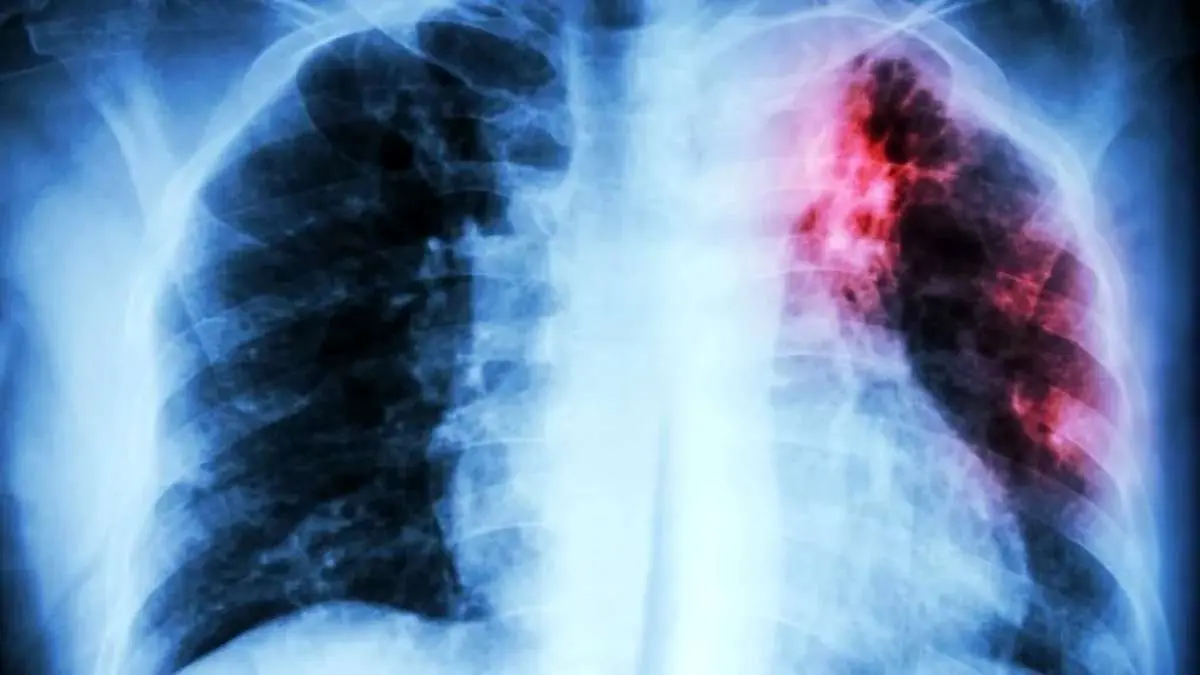

کشنده‌ترین بیماری عفونی جهان معرفی شد

سازمان بهداشت جهانی (WHO) اعلام کرد که بیماری سل (Tuberculosis) همچنان جایگاه مرگبار خود به‌عنوان کشنده‌ترین بیماری عفونی جهان را حفظ کرده و در سال ۲۰۲۴ جان ۱.۲۳ میلیون نفر را گرفته است.

به گزارش تابناک به نقل از برترین ها؛ براساس گزارش جهانی سل ۲۰۲۵، این بیماری عفونی در سال گذشته میلادی کشنده‌ترین بیماری عفونی بوده است. البته جهان برای نخستین‌بار پس از همه‌گیری کووید-۱۹، شاهد کاهش هم‌زمان موارد ابتلا به سل (نزدیک به ۲ درصد) و مرگ‌ومیر ناشی از آن (۳ درصد) بوده است. اما WHO هشدار می‌دهد که این دستاوردها شکننده هستند.